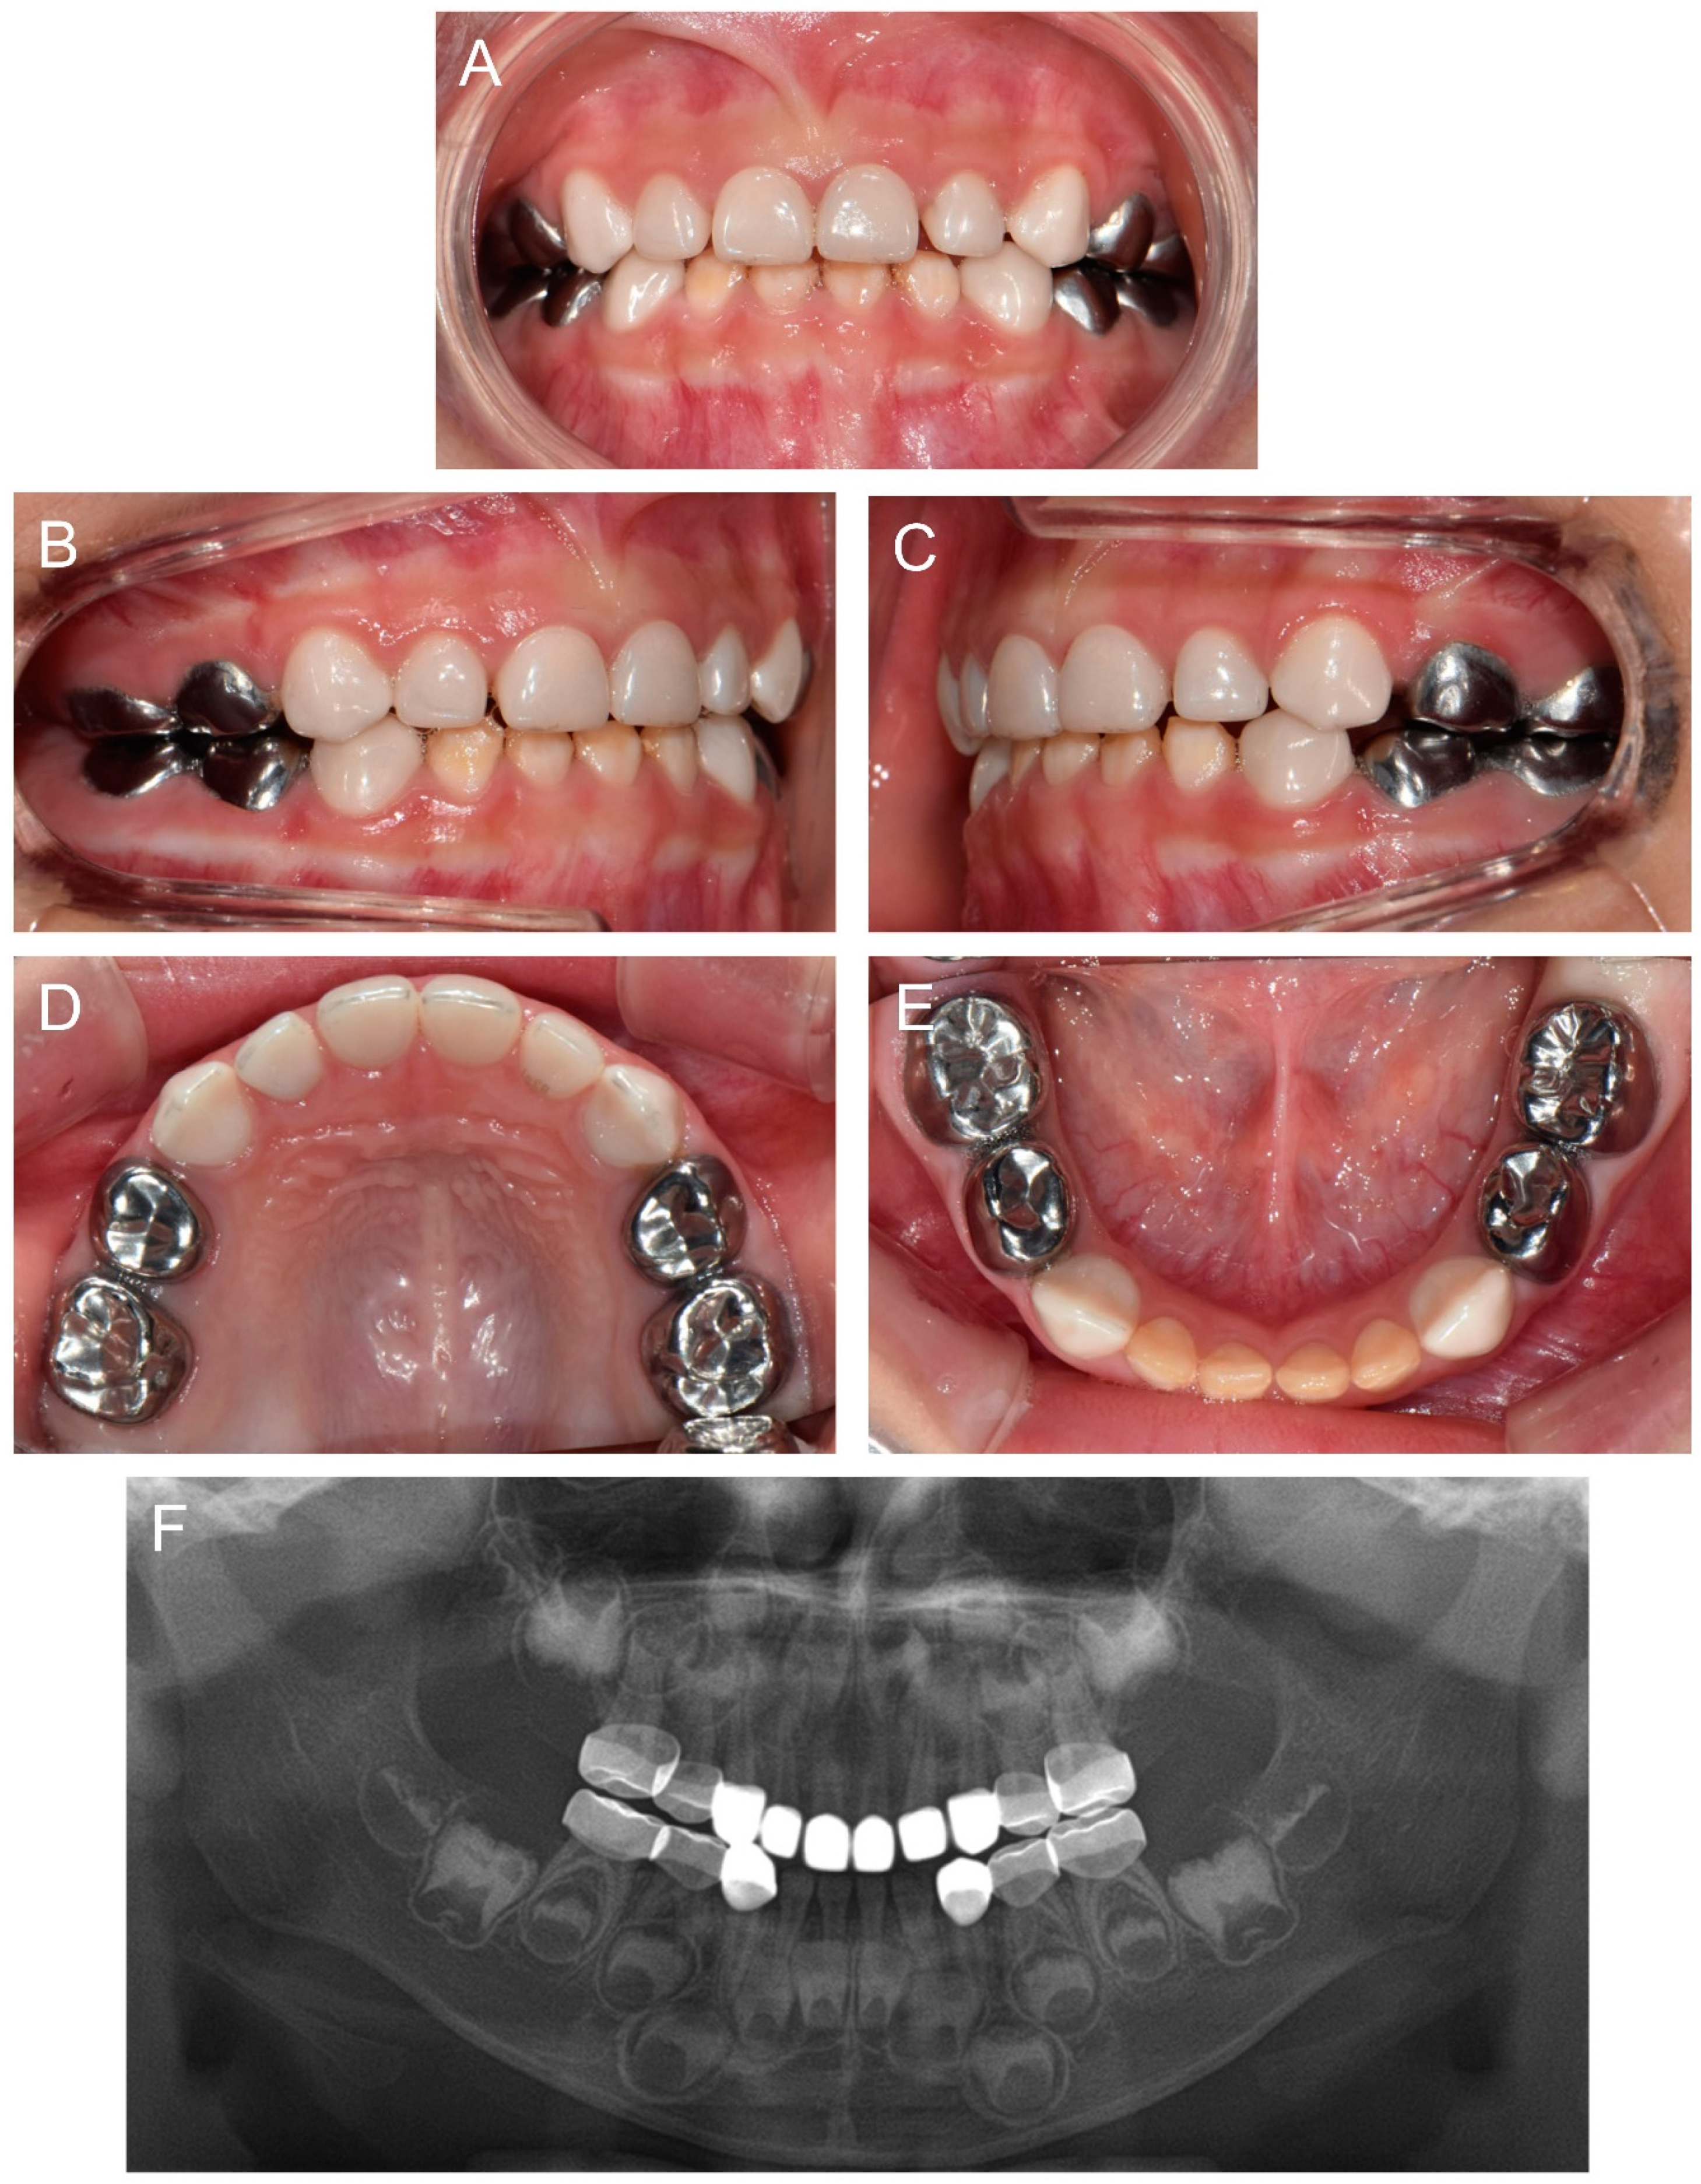

Figure 3.

Clinical photos and panoramic radiograph of the proband at age 3 years 11 months. (A–E) Oral health and restorations were well maintained. Anterior open bite was spontaneously corrected with the discontinuance of the finger sucking habit. (F) Panoramic radiograph showed hypocalcified enamel in the developing permanent teeth.